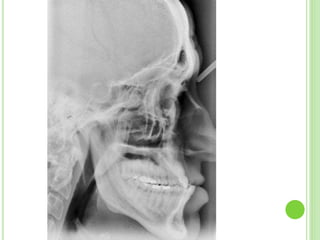

SKELETAL RELATIONSHIPS

Antero-posterior relationship

 The skeletal pattern is usually classIII

 The skeletal discrepancy may be exaggerated due to

forward displacement of mandible.

Vertical relationship

 Normal or increase or decreased.

SKELETAL---CLASS III